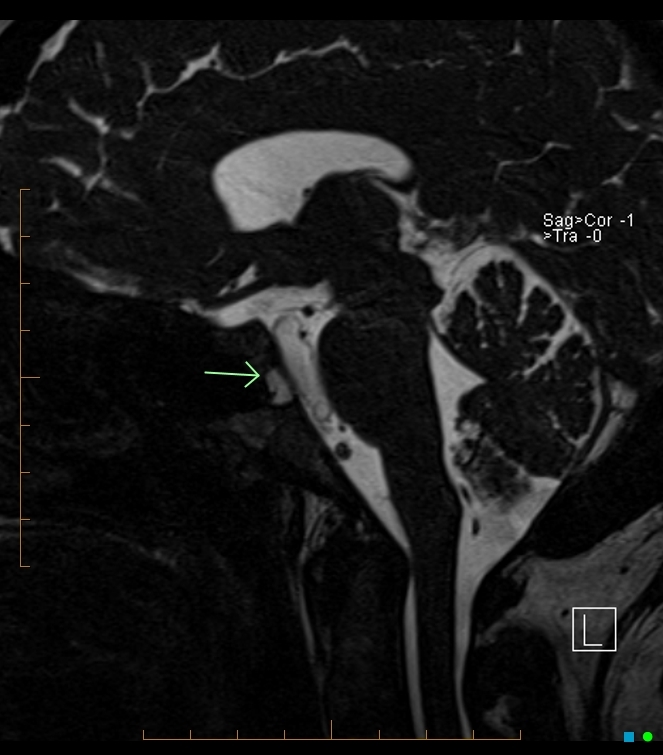

FIGURE 31-5 Basal encephalocele.A, A sagittal T1-weighted image shows callosal agenesis with a tiny lipoma (arrow). A large defect in the basisphenoid is seen. Note the apparent absence of the pituitary, floor of the third ventricle, and optic pathways. B, A high-resolution sagittal T2-weighted image shows the pituitary-hypothalamic structures (arrow) and optic pathways are contained within the encephalocele.